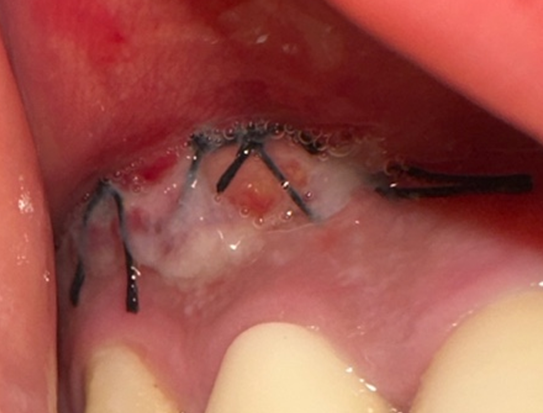

사진과 같이 잇몸을 절개 수술 후에 회복중에 있습니다...

사진과 같은 상태에서 흡연을 절대 하면 안되는건지 궁금합니다..!

피면 안되는걸 알지만.. 만약 흡연량을 조절해서 하루에 1-2개비 정도는 피워도 될까요...?

• 1번 째 사진